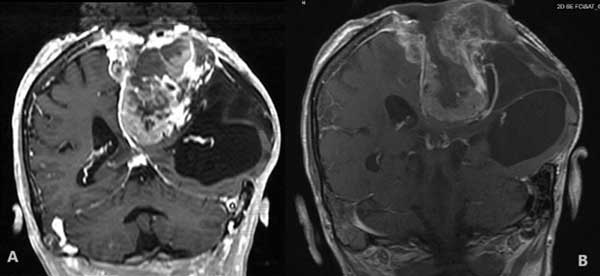

Paciente masculino, de 67 años, con antecedentes médicos de meningioma extremadamente agresivo y cirugías cerebrales previas. Fue ingresado con una historia de cambios cognitivos y del comportamiento con, aproximadamente, un mes de evolución, sumado a un empeoramiento progresivo del déficit motor del miembro superior izquierdo. La resonancia magnética mostró un tumor parasagital frontoparieto-temporal (FPT) derecho con regiones necróticas y efecto de masa (Figura 1).

Figura 1. Meningioma FPT parasagital izquierdo antes y después de cirugía. A) Resonancia magnética antes de cirugía, T1 con contraste. B) Resonancia magnética después de cirugía, T1.